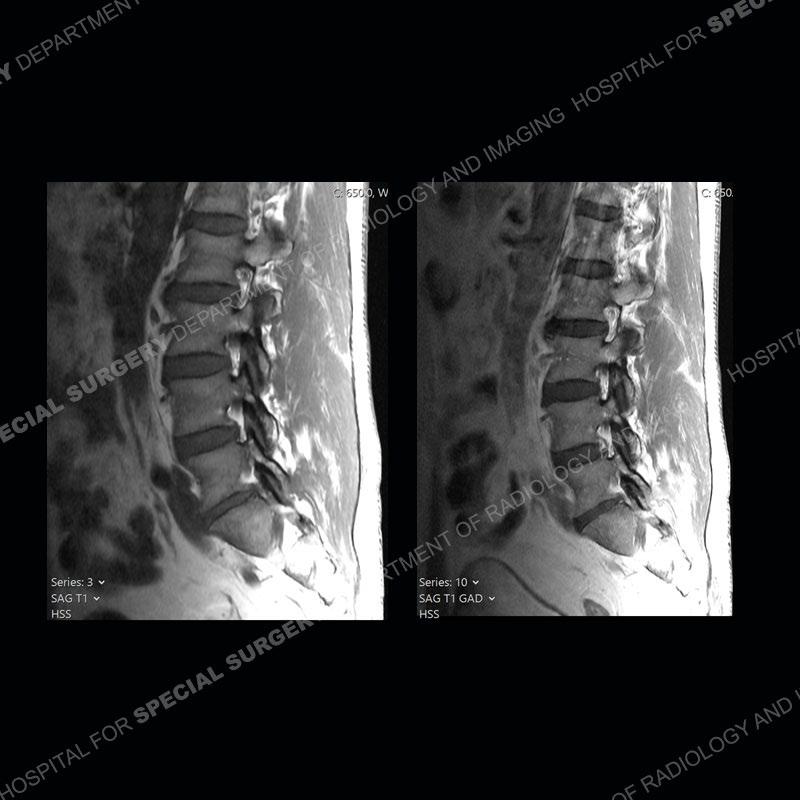

Post operative changes are seen on the left side at L5-S1 where there is near complete removal of the left sided L5 lamina, partial resection of the left L5-S1 facet joint, and resection of the left sided ligamentum flavum. In the anterolateral epidural space about the subarticular recess is a mass that demonstrates similar T1 and T2 signal characteristics to the adjacent degenerated disc. There is enhancement about the periphery of the mass, but the majority of this somewhat geographic or polyploid mass demonstrates no enhancement. The mass exerts prominent mass effect on the left S1 axillary sleeve/proximal nerve root. The left S1 nerve root shows enlargement and increased enhancement as compared to the contralateral right side.

Not as much of a diagnostic dilemma as some other cases but more so just a very nice example of what can be a difficult assessment at times. The evaluation of granulation tissue/scar/epidural fibrosis vs. disc herniation particularly in the earlier post operative period can be very difficult. Clues that can assist in identifying a disc herniation are a more geographic or polypoid nature to the mass, signal characteristics similar to the adjacent degenerated disc, mass effect upon the thecal sac/adjacent neural structures, and a typical enhancement pattern. As the disc material is avascular, as long as imaging is performed in a relatively rapid fashion after contrast administration (within 20-30 minutes), the granulation tissue around the disc will enhance but the disc material itself will not. If there is a marked delay between contrast administration and imaging, there may be diffusion of contrast into the disc making the assessment very difficult. The marked utility of contrast to help delineate disc vs. scar has led to our institution employing contrast fairly uniformly within the first two years following surgery.

The scar tissue in the setting of prior disc removal will be present in the anterior and anteriorlateral aspect of the epidural space. The signal characteristics can be somewhat variable from slightly more T2 hyperintense earlier on to T2 hypointense as the scar matures. However, the signal does not tend to follow the adjacent degenerated disc. The scar can produce mass effect, but it does not have to do so. In addition, at times the scar may be associated with a retraction of the adjacent thecal sac. Given the vascular nature of the scar there is typically somewhat avid, uniform enhancement which occurs fairly rapidly after contrast administration and begins to diminish within 20 minutes or so. Trying to discern the difference between scar and disc is of paramount importance given the rather poor outcomes associated with resection of scar as compared to disc material.